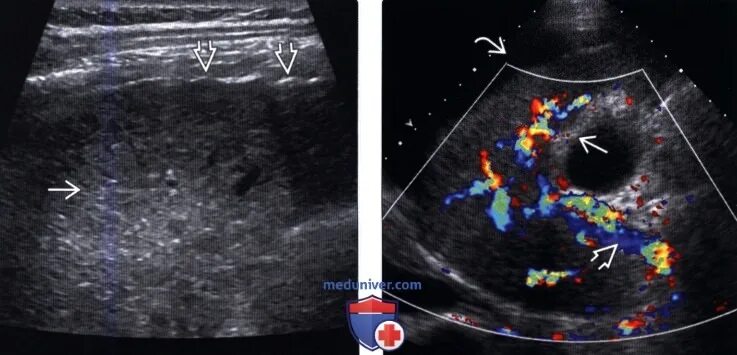

Очаги регенерации